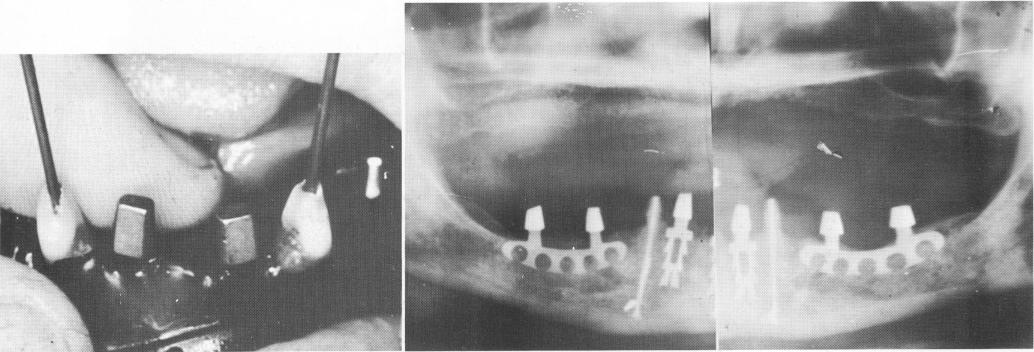

Fig. 13-58. Four blade implants were tapped into the bone.

Two narrow blade implants were placed mesially to the two cuspids, and two double-posted blades

Fig. 13-59. A, Endodontic stabilizers were introduced into the cuspids. The teeth and implants are protected from the saliva with the use of rubber dams. B, An immediate postoperative radiograph.